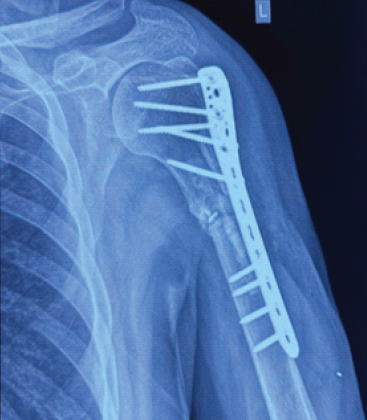

Successful Management of a 40-Year-Old Non-union of the Humeral Shaft with Pseudoarthrosis with Plate Fixation and Bone Grafting: A Case Report

Deepak Kumar , Omprakash Meena , Vasu , Ajay Shukla , Manjesh Reddy S V